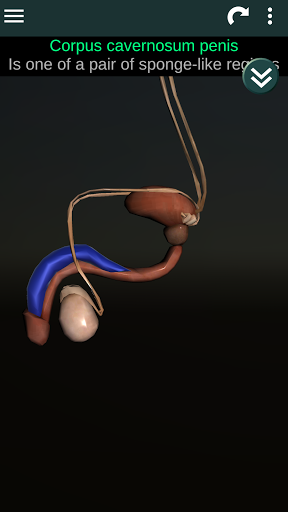

Internal Organs in 3D Anatomy لـ Vodafone Smart N9 Lite

(الأجهزة الداخلية في)

Internal Organs 3D Anatomy 3.4

يمكنك هنا تنزيل ملف حزمة تطبيق أندرويد "Internal Organs 3D Anatomy" الخاصة بجهازVodafone Smart N9 Lite مجانًا، نسخة ملف حزمة تطبيق أندرويد - 3.4 للتحميل على Vodafone Smart N9 Lite اضغط ببساطة على هذا الزر. إنه سهل وآمن. نحن نقدم فقط ملفات حزمة تطبيق أندرويد الأصلية. إذا انتهكت أية مواد موجودة في الموقع حقوقك قم بإبلاغنا من خلال